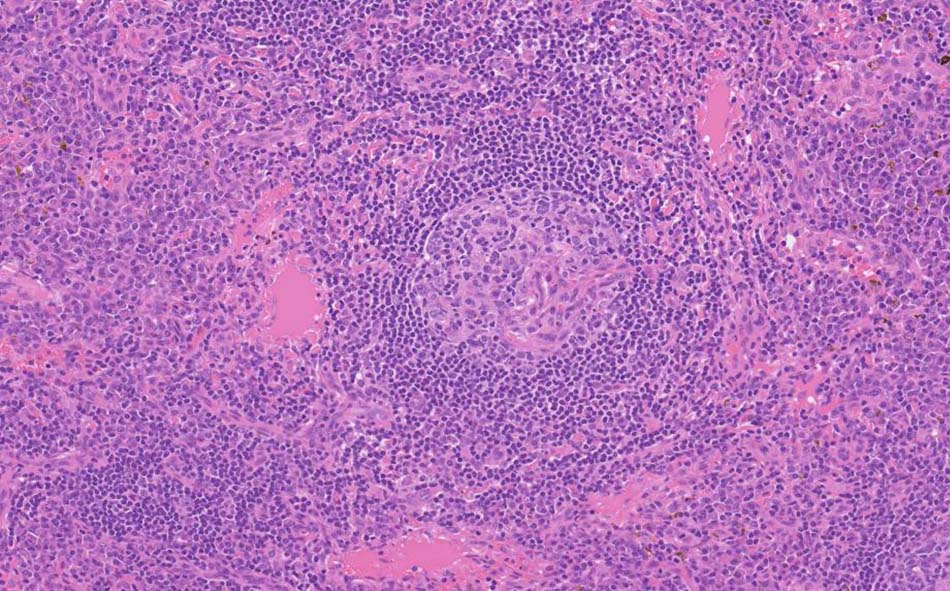

12 x 3.8mm, 腫大した鼠径リンパ節が生検された.--クリックで大きな画像がみられます.|

萎縮した胚中心をマントル細胞が取り囲む濾胞構造がびまん性に認められる. 濾胞間には,形質細胞が密に認められる.

萎縮した胚中心には細血管が侵入する特徴的な所見がある. (Lolli-pop germinal center)

免疫染色; リンパ節のplasma cellは多くがIgGが陽性. さらにIgG4陽性plasma cellsが多数をしめる.